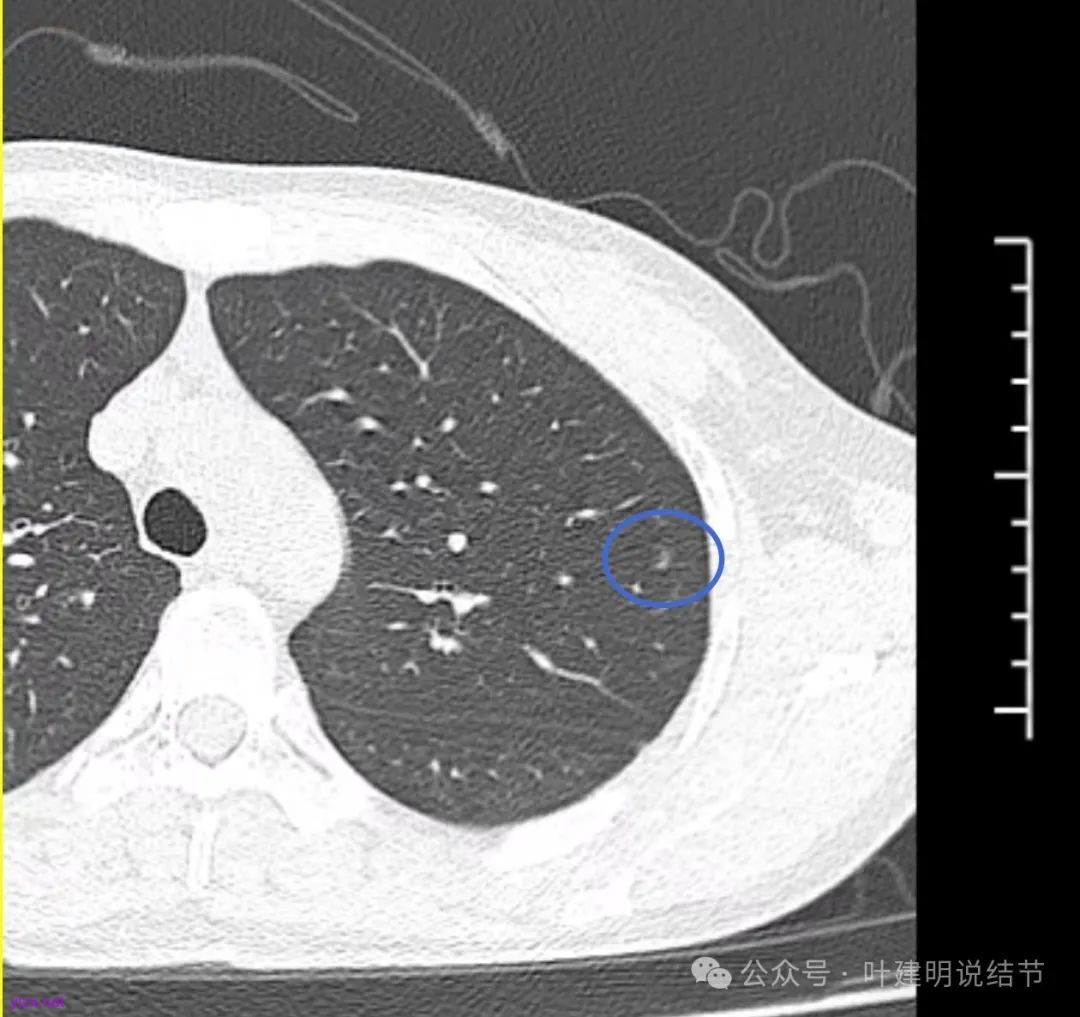

先来看2024年12月的影像:

左上叶淡而轮廓欠清楚的磨玻璃结节,缺乏聚拢性,没有收缩力。

在上叶淡而轮廓较清,密度不太纯略显杂乱的小磨玻璃结节。

右下叶磨玻璃结节伴空泡征,轮廓较清,瘤肺边界清楚。